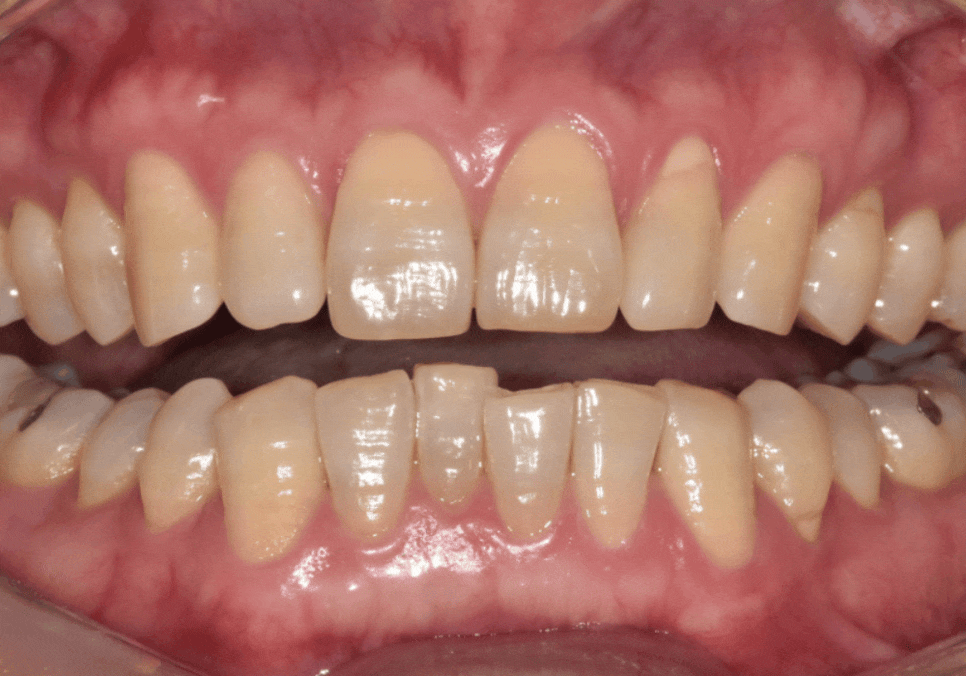

230613 (전) 250721 (후)

치료 전, 안으로 쑥 들어가 있어

전체적인 배열을

비뚤비뚤하게 만들었던 앞니가

제자리를 찾은 모습입니다.